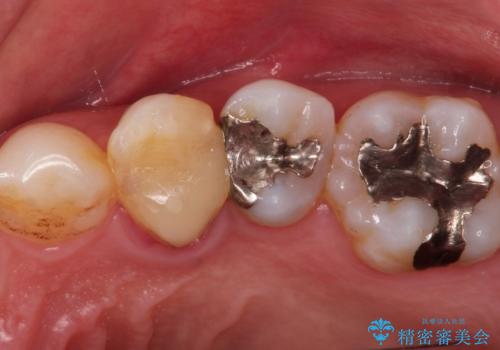

- 昔入れたメタルインレーの下にむし歯が再発したため治療を行った患者様です。

メタルインレーは汚れが付着しやすく、適合も悪いことがあるため、むし歯が再発しやすかったと思われます。

フロスなどの日常の清掃はもちろん不可欠ですが、メタルインレーより汚れが付着しずらいセラミックインレーにて今回は治療を行いました。